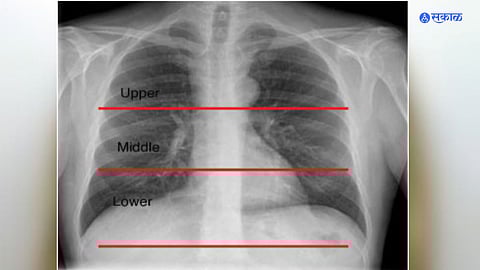

नवी दिल्ली : शरीरातील विविध समस्यांचे निदान करण्यासाठी ‘एक्स रे’चा वापर केला जातो. मात्र, आता संशोधकांनी कृत्रिम बुद्धिमत्तेच्या मदतीने छातीच्या एक्स रे वरून संबंधित व्यक्तीच्या वयाचा अंदाज बांधू शकणारे नवीन मॉडेल विकसित केले आहे. यासंदर्भातील संशोधन ‘द लॅन्सेट हेल्दी लाँगेविटी’ या नियतकालिकात प्रसिद्ध झाले आहे. जपानमधील ओसाका मेट्रोपॉलिटन युनिव्हर्सिटीतील संशोधकांनी हे मॉडेल विकसित केले.

हे एक्स रे चे नवीन मॉडेल व्यक्तीच्या वयाबरोबरच उच्च रक्तदाब आणि ‘क्रॉनिक ऑब्स्ट्रक्टिव्ह पल्मोनरी डिसीज’ सारख्या फुफ्फुसांच्या आजारांविषयीही सूचित करू शकते. कृत्रिम बुद्धिमत्तेवर आधारित एक्स रेच्या मॉडेलने वैद्यकीय प्रतिमा प्रणालीत (मेडिकल इमेजिंग) मोठी झेप घेतली असून आजारांचे लवकर निदान होऊन वेळीच उपचार करण्याचा मार्गही मोकळा झाला आहे.

संशोधकांकडून २००८ ते २०२१ दरम्यान आरोग्य तपासणी करणाऱ्या सुमारे ३६,०५१ व्यक्तींचे ६७,१०० एक्स रे काढून कृत्रिम बुद्धिमत्तेवर आधारित मॉडेल विकसित केले. यावेळी या एक्स रेने वर्तविलेला वयाचा अंदाज व व्यक्तीचे कालानुक्रमानुसार किंवा प्रत्यक्षातील वय यात नजीकचा सहसंबंध असल्याचेही संशोधकांना आढळले.

त्याचप्रमाणे या एक्स रेने वर्तविलेला वयाचा अंदाज व व्यक्तीचे वय यातील फरक उच्च रक्तदाब, सीओपीडी, हायपरयुरिसेमिया (रक्तातील युरिक ॲसिडची उच्च पातळी) आदींशी जवळचा संबंध असल्याचेही निदर्शनास आले. कृत्रिम बुद्धिमत्तेवर आधारित एक्स रेने वर्तविलेले वय जेवढे अधिक तेवढे संबंधित व्यक्तीला वरील आजार होण्याची शक्यता अधिक आहे, असा याचा अर्थ असल्याचे संशोधकांनी स्पष्ट केले.

कृत्रिम बुद्धिमत्तेवर आधारित एक्स-रे केवळ शरीरातील अवयव व हाडांची स्थितीच दर्शवीत नाही तर तो वय तसेच दीर्घायुष्याबाबत अंदाज वर्तविण्यासाठीही उपयुक्त ठरू शकतो. हे तंत्रज्ञान अधिक विकसित करून जुनाट आजारांच्या तिव्रतेचा तसेच आयुर्मानाचा अंदाज घेण्यासाठी ते वापरण्याचे आमचे उद्दिष्ट आहे.